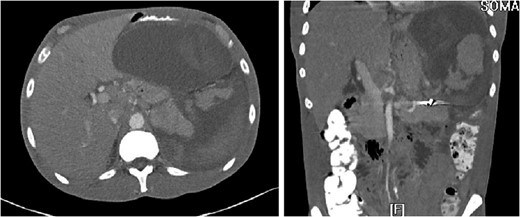

The ‘Islands’ of preserved spleen lit up with IV contrast surrounded by a large collection of old blood and devitalized tissue.

3D reconstruction and coronal CT after placement of pigtail drainage catheter.

Our patient was vaccinated given that post-procedure CT showed the spleen to be partially necrotic with only two islands of well-perfused, preserved spleen depicting >15% decrease in splenic volume. The plan was to perform interval splenectomy however he was lost to follow up.